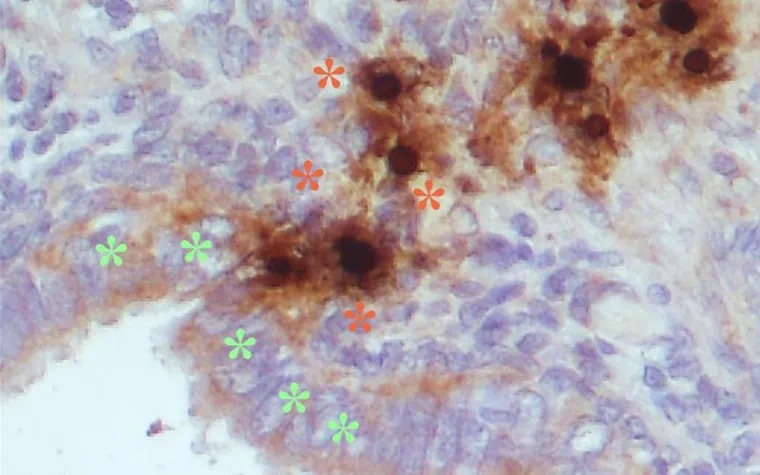

In der Studie konnten Müller und das Team zeigen, dass PIF die Entzündungsreaktion beeinflusst und je nach Umfeld die Endometriosezellen absterben. Damit kann das Molekül potenziell sowohl in der Diagnostik als auch in der Therapie von Endometriose eingesetzt werden. «Wir möchten diesen neuen Ansatz weiter verfolgen, die Entzündungen, die der Ursprung der Endometriose sind, an der Wurzel zu packen», sagt Prof. Dr. med. Michael Mueller, Chefarzt Gynäkologie und gynäkologische Onkologie an der Frauenklinik in Bern.